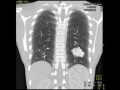

This is a patient who presents with recurrent nose bleeds and shortness of breath. A frontral radiograph of the chest was obtained which demonstrates a mass in the left lower lobe as indicated by the red arrows. To further evaluate this mass, a contrast enhanced CT of the chest was obtained. The second image is a maximum intensity projection reconstruction in the coronal plane in lung windows. The lobulated mass in the left lower lobe is similar in attenuation to the small surrounding pulmonary vessels and its morphology resembles a tangle of large vessels. The third image is a maximum intensity projection reconstruction of the chest in the coronal plane. The red arrow demonstrates the branch of the left lower lobe pulmonary artery that feeds the lesion. The green arrow indicates the dilated left lower lobe pulmonary vein that drains the lesion. The findings are most compatible with a large pulmonary arteriovenous malformation. Pulmonary arteriovenous malformations as well as recurrent nose bleeds are seen in a condition known as hereditary hemorrhagic telangiectasias, which is also known as Osler-Weber-Rendu syndrome. These patients acquire arteriovenous malformations throughout the body and brain. Pulmonary arteriovenous malformations are treated with coil embolization to prevent complications such as strokes as well as brain abscesses.